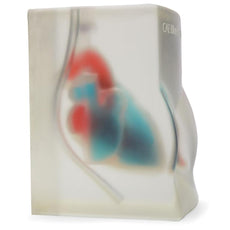

Brand New! 2nd Generation upper torso ultrasound guided central line placement training model with transparent tissue insert allows users to develop and practice the skills necessary to gain proficiency in using ultrasound to guide central catheter insertions in the internal jugular vein (IJ), subclavian vein, and axillary vein while revealing the venous and arterial vessels as well as accessory boney structures. Developed with the goal of helping clinicians bridge the learning gap by allowing them to see the internal anatomical structures with their eyes as well as with ultrasound imaging, our transparent central line placement tissue offers superb ultrasound hands-on training. Using Blue Phantom proprietary simulated human tissue, this very realistic and ultra-durable transparent central venous access ultrasound training model is excellent for training clinicians in the psychomotor skills associated with ultrasound guided central line placement procedures. These ultrasound imaging skills include; using ultrasound system controls, transducer positioning and movement, recognition of arterial and venous anatomy, using ultrasound to target the appropriate vessels for cannulation, and performing a central venous access procedure.Helps

clinicians bridge the learning gap by allowing them to see the internal anatomical structures with their eyes as

well as with ultrasound imaging.

- Developed with the goal of helping clinicians bridge the learning gap by allowing them to see the internal anatomical structures with their eyes as well as with ultrasound imaging

- Tissues match the acoustic characteristics of real human tissue so when you use your ultrasound system on our training models, you experience the same quality you expect from imaging patients in a clinical environment

- Developed with the goal of helping clinicians bridge the learning gap by allowing them to see the internal anatomical structures with their eyes as well as with ultrasound imaging

- Tissues match the acoustic characteristics of real human tissue so when you use your ultrasound system on our training models, you experience the same quality you expect from imaging patients in a clinical environment